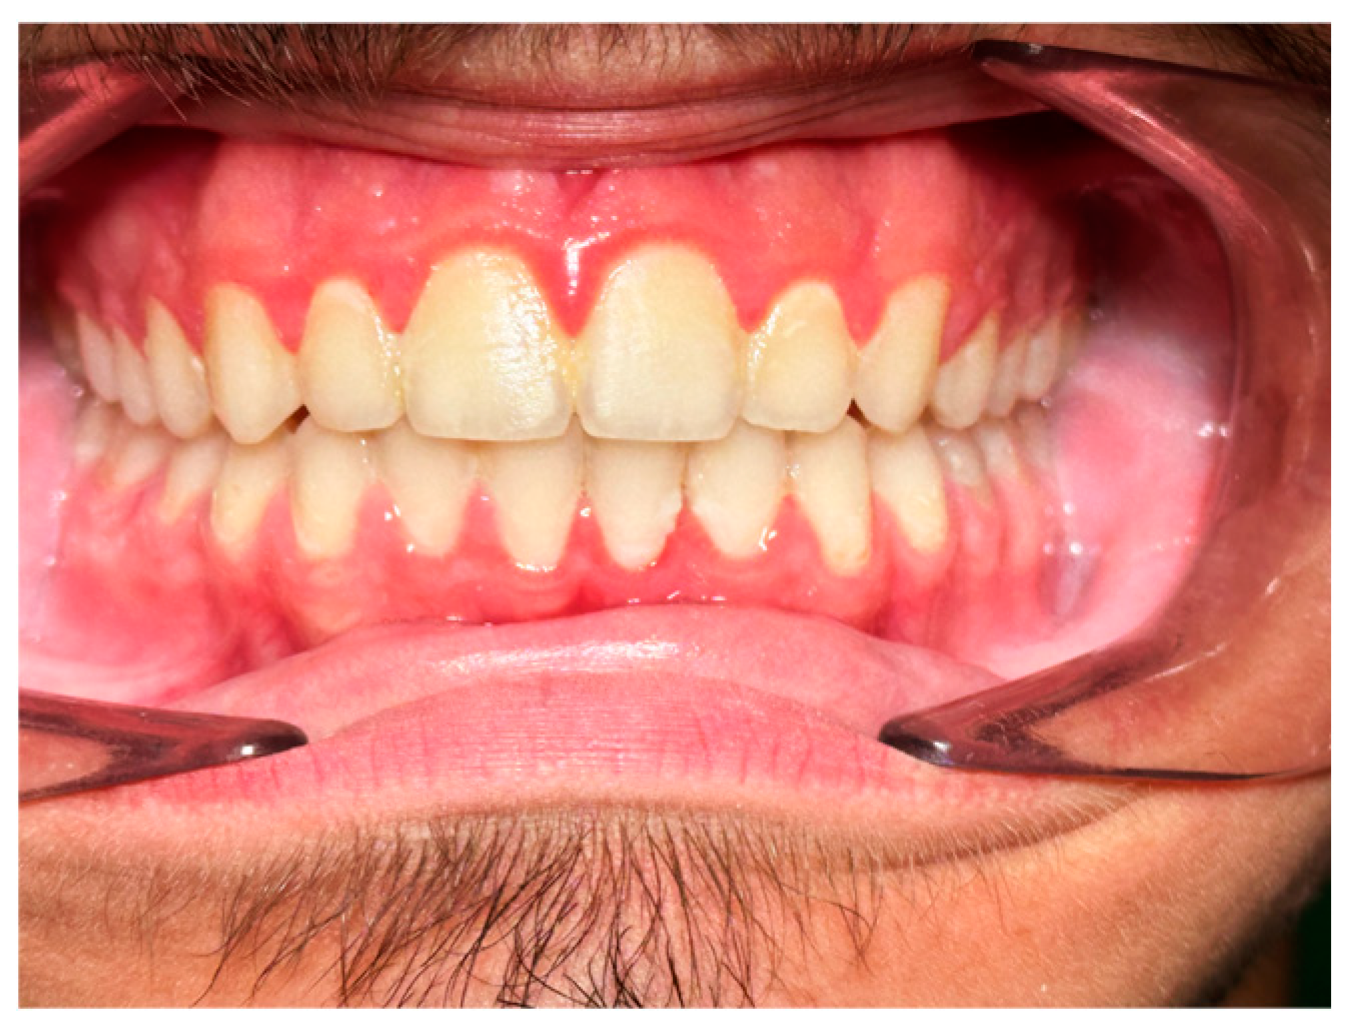

The treatment was concluded with good results in terms of intercuspation, muscular and joint wellbeing status assessed by a clinical chart including muscle palpation, evaluation of mouth opening and closing dynamics (

Figure 8,

Figure 9 and

Figure 10).